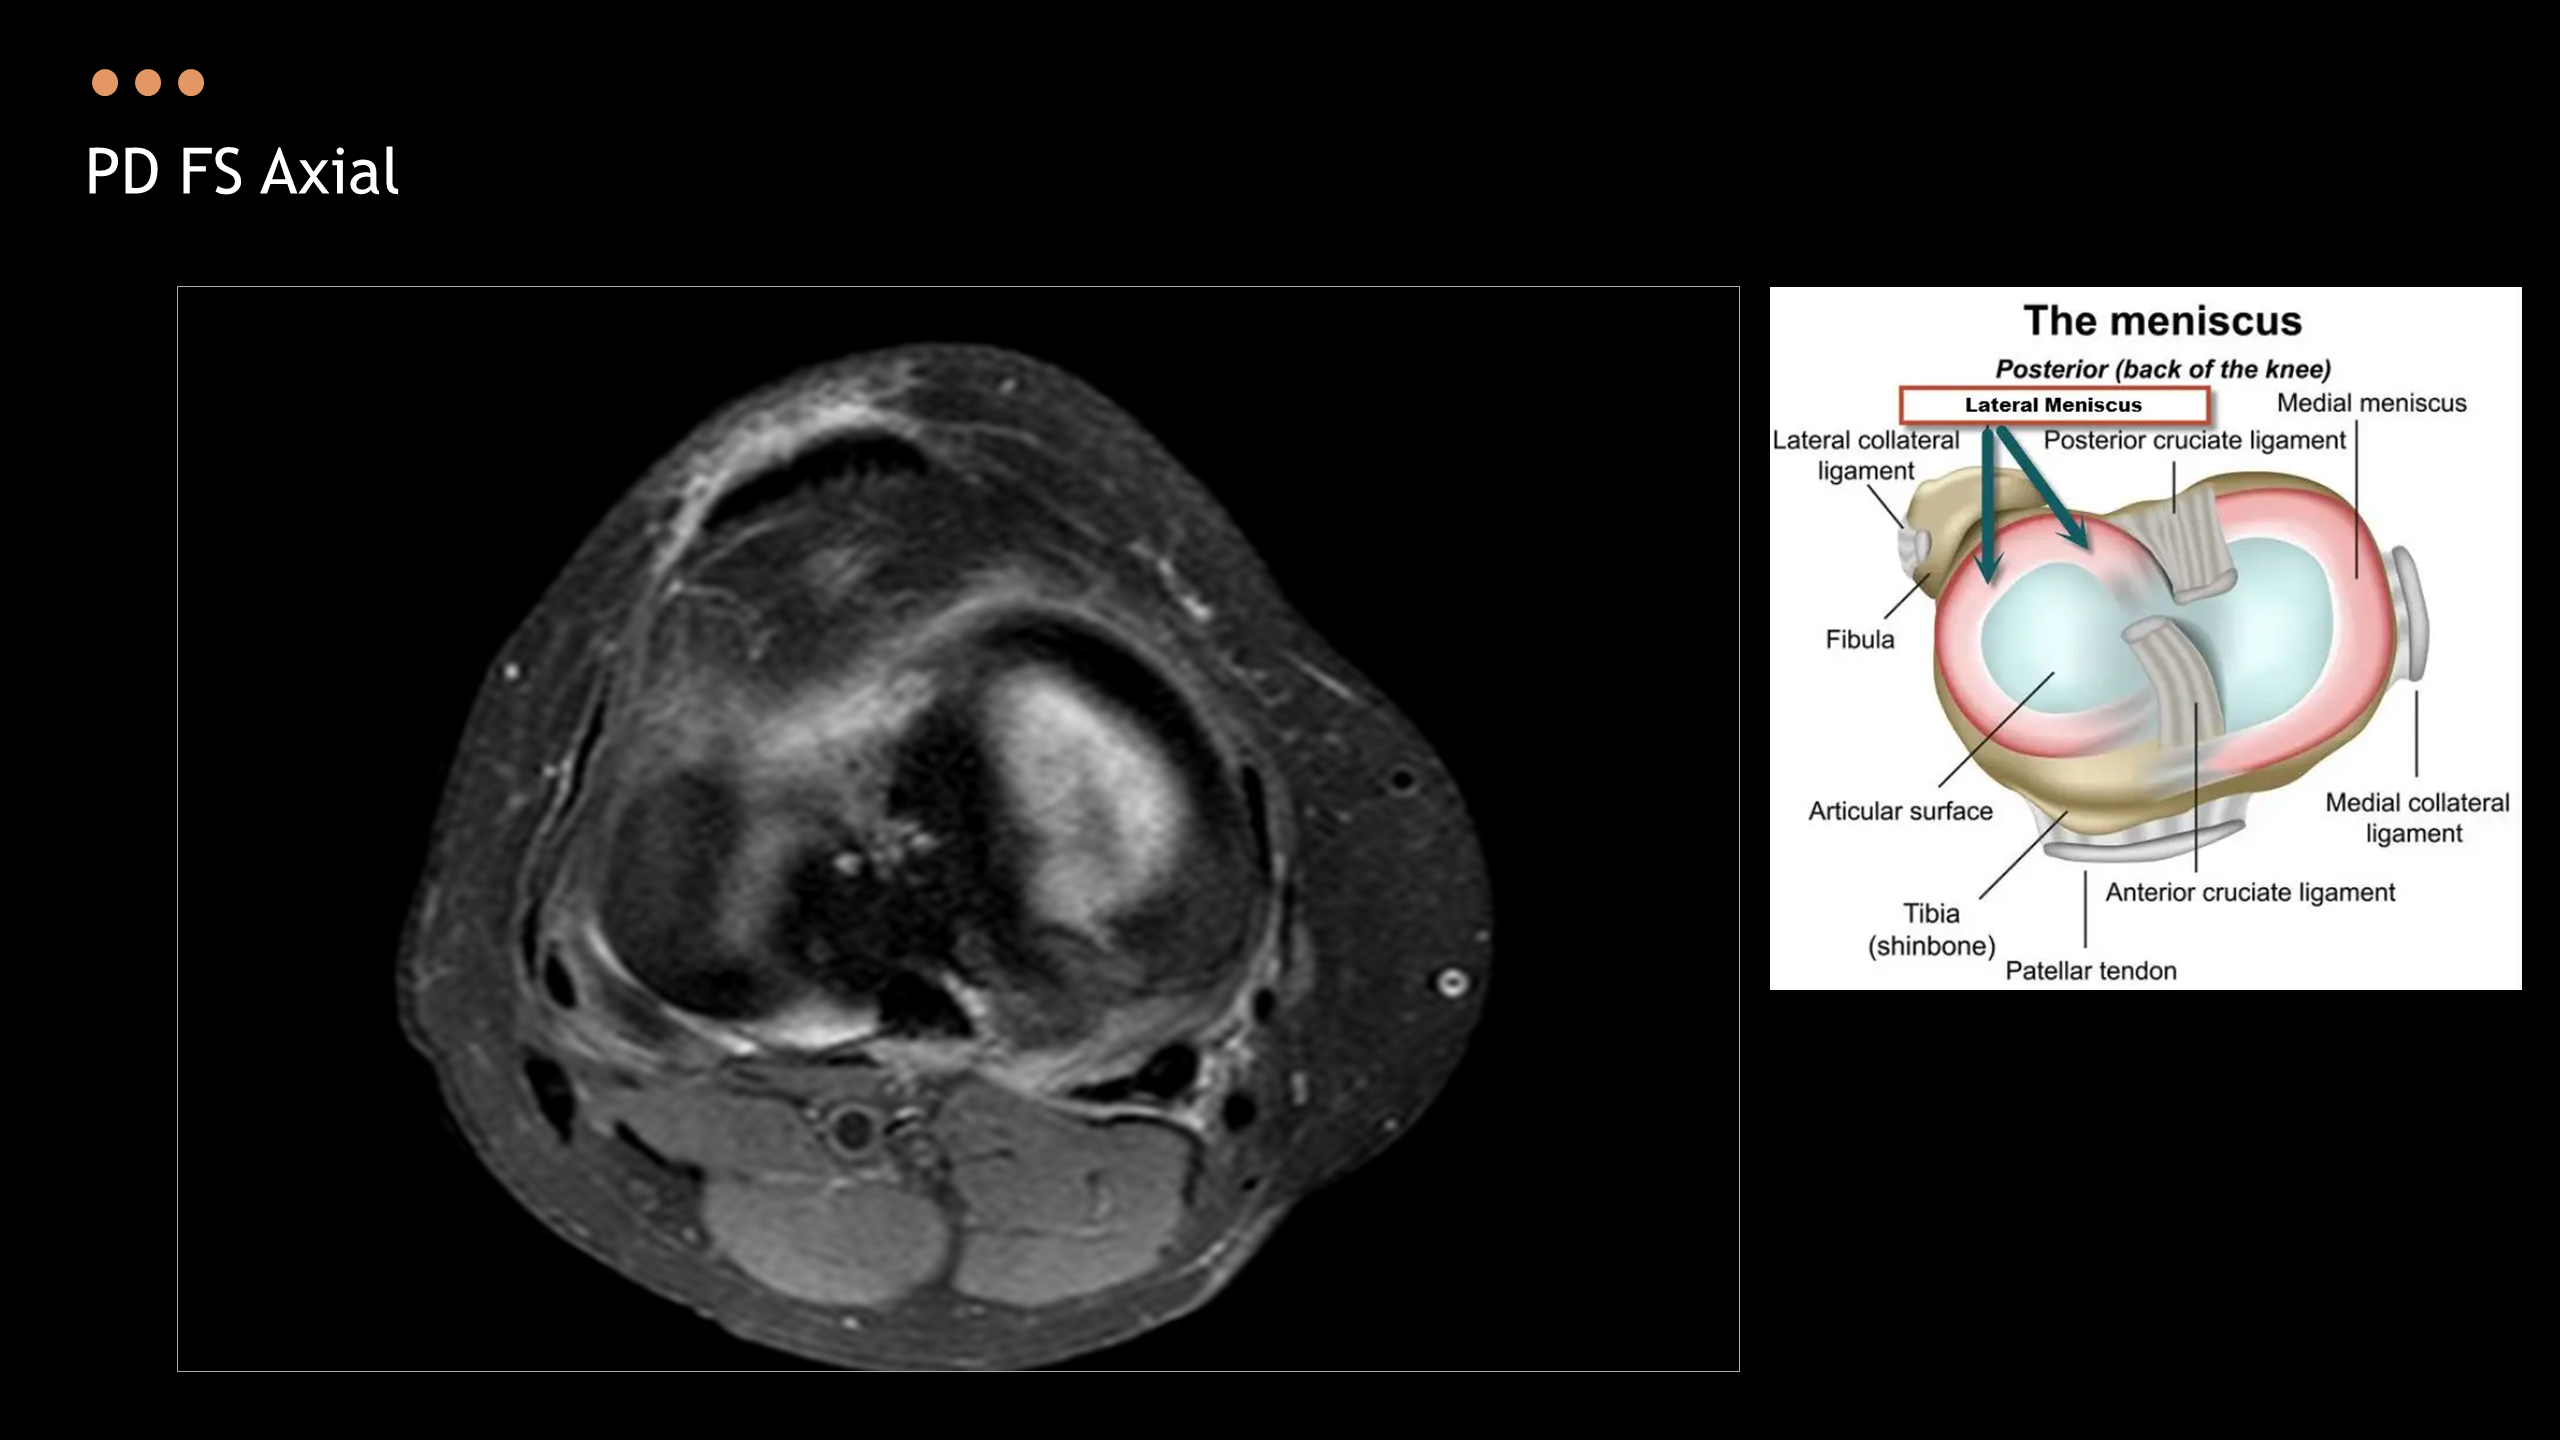

아래의 Normal Knee MR Anatomy를 숙지하고 오셔야, 강의에 어려움이 없습니다.